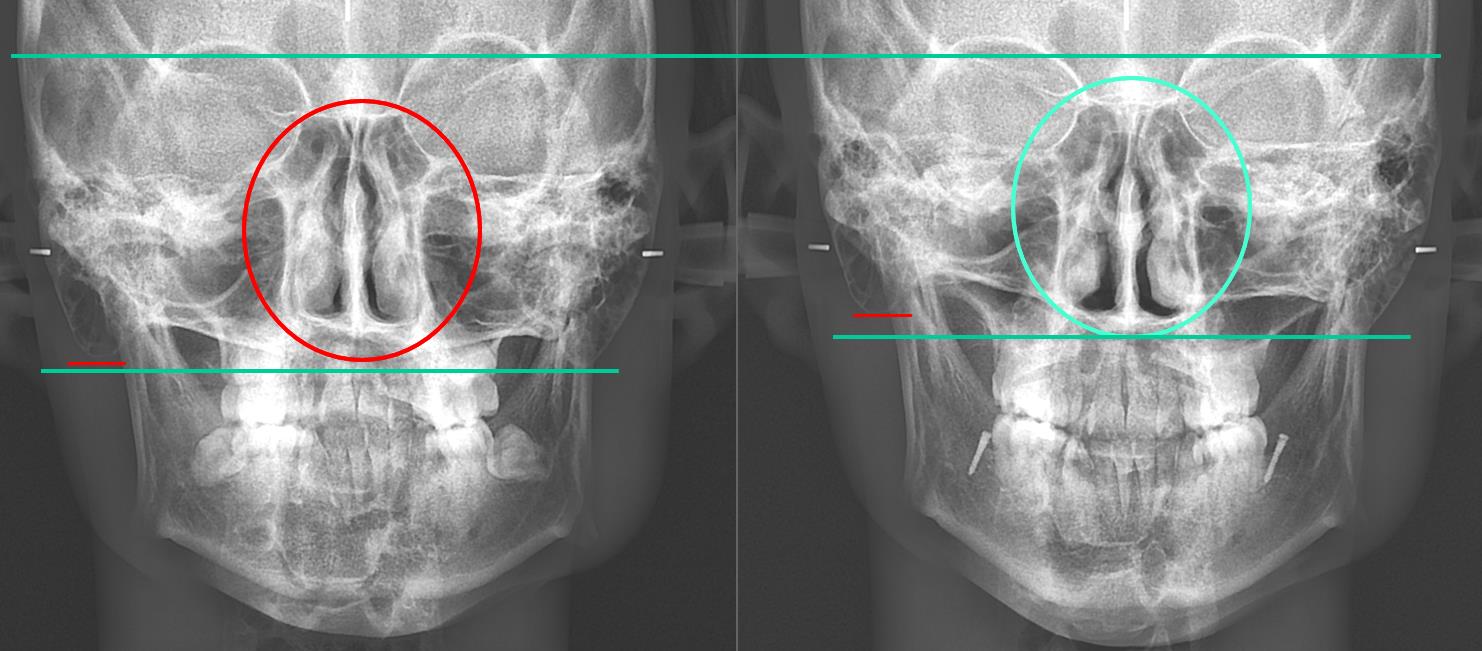

When the three-dimensional position of the mandible is aligned with the facial midline and the teeth are arranged accordingly, the following changes occur.